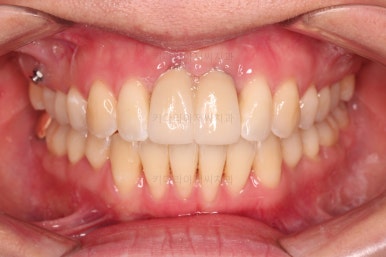

4. 마무리

앞니 임플란트의 색깔, 모양 등으로 몇 번의 수정 작업을 거친 뒤, 치료를 종료합니다.

잇몸뼈의 상태에 비해 매우 양호하게 임플란트가 완성되었고요.

개방교합, 2급 부정교합 등 모든 면에서 개선이 잘 되었습니다.

부산개방교합 전후 비교를 해보겠습니다.

웃을 때 잇몸선이 거의 보이지 않아 잇몸의 레벨이 위에 있었던 점이 완벽히 가려졌고요.

얼굴모습의 변화를 보면 거의 완벽하다 싶을 정도의 치료가 된 것이 아닌가 싶습니다.

앞니의 위치, 교합 개선, 웃는 모습 개선, 입매, 돌출감 개선, 옆선 등등 치료가 매우 고난도였던점을 생각한다면 이보다 더 좋은 교정 + 앞니 임플란트가 없다 싶을 정도의 치료였습니다.

임플란트 완료까지 총 3년 걸렸으며 앞니 제외 추가 발치는 없이 부산개방교합 교정하였습니다.